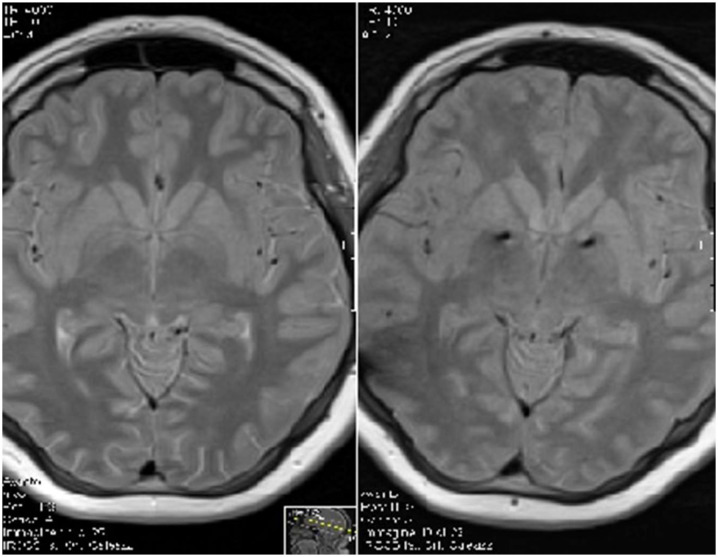

To date, no consensus has been reached regarding the optimal anatomical target for stimulation. Based on clinical experience and accumulated data, the medial (limbic) aspect and the anterior part of the globus pallidus internus (GPi) appear to be the most promising targets (Figure 2). Alternative targets, applied either singly or in combination, have included the posteroventral (motor) GPi, thalamus, the anterior limb of the internal capsule (ALIC), nucleus accumbens (NA), and the subthalamic nucleus (STN), with varying degrees of clinical success [ref. 99]. The Montpellier groupintroduced a dual-targeting approach involving the simultaneous implantation of electrodes in both the medial and dorsolateral GPi, aimed at addressing the limbic and motor symptomatology of GTS, respectively, however, only one single case was reported [ref. 100,ref. 101]. At our institution, we have developed the concept of “rescue surgery,” referring to a second surgical intervention performed in refractory patients who derive insufficient benefit from their initial DBS implantation [ref. 102]. One of the major challenges in identifying a universal target is the significant inter-individual variability in the neuropsychiatric comorbidities associated with GTS, including OCB, OCD, ADHD, depression, and anxiety [ref. 102]. Whether these comorbidities should serve as exclusion criteria for DBS remains a matter of ongoing debate.